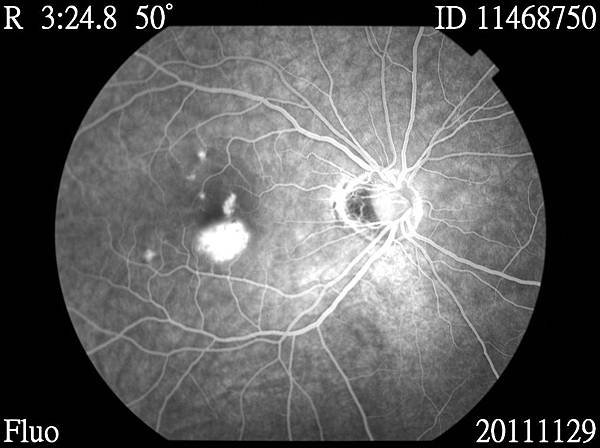

11468750_20111129_142518_Redfree_R_001.JPG 11468750_20111129_142737_Fluo_R_001.JPG 11468750_20111129_142746_Fluo_R_001.JPG 11468750_20111129_142954_Fluo_R_001.JPG 11468750_20111129_143002_Fluo_R_001.JPG 11468750_20111129_143009_Fluo_R_001.JPG 11468750_20111129_143031_Fluo_R_001.JPG 11468750_20111129_143749_Fluo_R_001.JPG 11468750_20111129_143818_Fluo_R_001.JPG

醫生說,我的黃斑部新生血管,需要眼內注射藥物去抑制他繼續增生,還有,視網膜周圍變薄了,需要先做雷射把他圍起來,避免將來破掉.....

至於新生血管的部份,要再做脈絡膜的檢查...因為我不只新生血管,旁邊還有好幾個點,這是比較奇怪的....